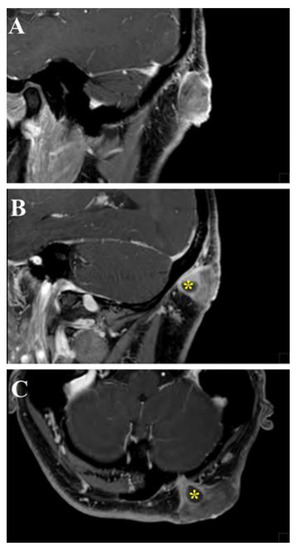

| Umana et al., 2021 | 1 | 45M | Occipital scalp | Psammomatous meningioma | Surgical resection | No recurrence at 6 months | Complete recovery |